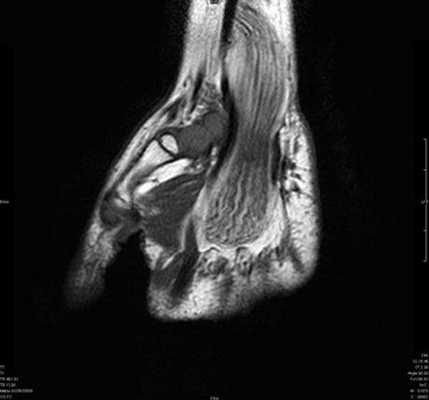

Синдром повреждения сухожилий включают частичные и полные их разрывы, проявления теносиновита и посттравматического тендиноза. Основную долю составляют теносиновиты, возникающие изолированно или на фоне повреждения костей и связок. Морфологически теносиновиты характеризуются скоплением синовиальной жидкости под оболочками сухожилия. Рентгенодиагностика в диагностике теносиновитов неинформативна. Наиболее информативны в диагностике теносиновита УЗИ и МРТ.

Теносиновит сухожилий глубокого сгибателя пальцев кисти и длинного сгибателя большого пальца.